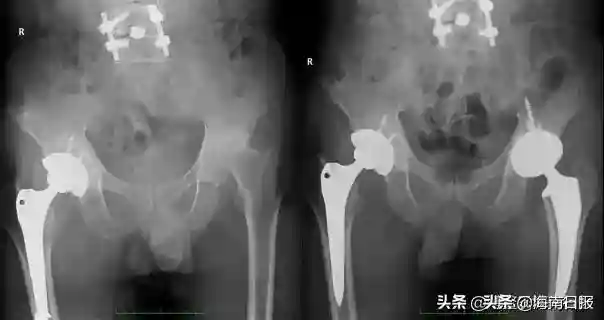

患者髋关节术前(左),术后(右)x光照片

此次手术中的患者已有66岁,患类风湿关节炎长达50年,常年服用激素和免疫抑制剂造成了包括股骨头坏死、骨质疏松等一系列并发症。手术前,老人已做过三次大的骨科手术,此前的手术和股骨头坏死让老人双腿长度差达到1公分以上,老人行走一瘸一拐而且伴随钻心的疼痛。

“患者体质弱,还伴有高血压、肺气肿等一系列疾病,对手术及术后康复来说是严峻的挑战。”操刀实施手术的解放军总医院骨科教授柴伟表示,团队术前利用人工智能技术针对风险进行了一系列排查,并制定了详尽的康复方案,并对患者的假体型号、截骨位置、肢体长度等参数进行了精准测量,确保手术地顺利进行。

在经过45分钟手术后,柴伟带领手术团队为患者成功施行了全髋关节置换术,其中切口长度仅7cm,出血不到100ml。9月19日,该患者在完成手术后的第一天就完成下地站立、迈步行走等,他说,“手术一点都不疼,创口也小,走路也不瘸了,感觉非常好!”